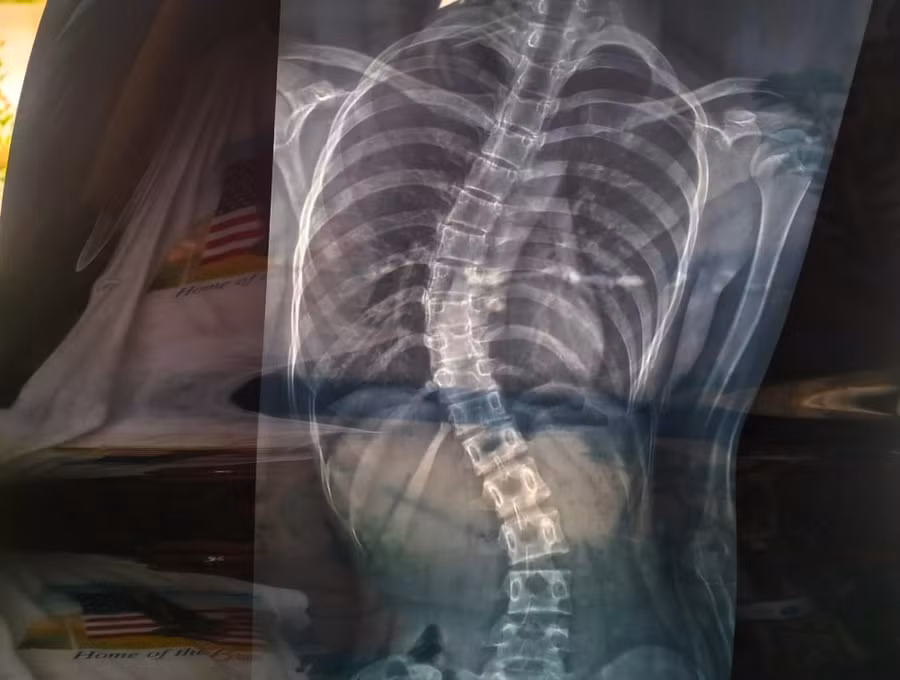

Theo gợi ý của bạn bè và hàng xóm, tôi đưa con gái lên TPHCM thăm khám. Qua hình ảnh X.Quang, bác sĩ chẩn đoán Hoàng Yến bị “vẹo cột sống”, chỉ định phẫu thuật điều trị càng sớm càng tốt (chi phí phẫu thuật khoảng 200 triệu đồng) nếu không sẽ ảnh hưởng rất nhiều đến sức khỏe và mọi sinh hoạt sau này”.